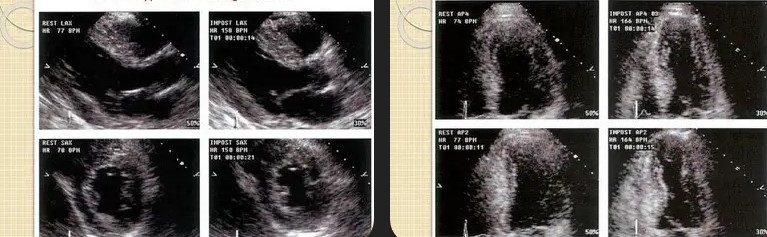

Stress Echocardiograms

Both treadmill and dobutamine options available for accurate evaluations.